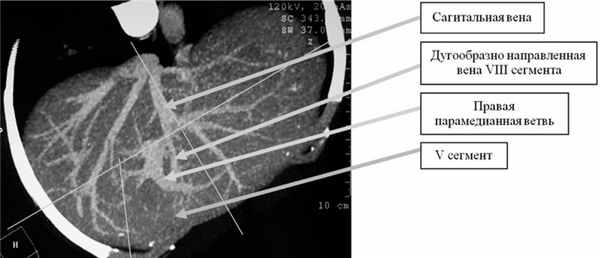

Ствол ВВ делится на правую и левую ветвь I порядка под углом 90—180° (125,0±21,5°). В 219 (84,2%) случаях правая бранша ВВ дихотомически разделялась на правую парамедианную и правую латеральную вены. Правая парамедианная вена отходит от передней верхней поверхности правой ВВ и принимает восходящее направление, уходя вглубь печени, снабжая кровью V и VIII сегменты, в то время как правая латеральная вена снабжает кровью VI и VII сегменты (рис. 1). Рис. 1. Больной С., 76 лет. Прямая портограмма. Видно деление правой бранши воротной вены.

С хирургической точки зрения атипичная резекция V сегмента не является трудоемкой операцией, но сегментэктомия в пределах его анатомических границ представляет собой сложную задачу и в большинстве случаев невыполнима. Объясняется это не только тем, что этот сегмент занимает небольшой участок паренхимы правой доли печени, но и дугообразным прохождением через его ткань вверх правой парамедианной вены. Последняя идет по направлению к диафрагмальной поверхности печени и отдает конечные ветви к V и VIII сегментам (см. рис. 1 и 2). Рис. 2. Больной Р., 49 лет. Компьютерная портокаваграмма. Кровоснабжение V и VIII сегментов печени.

Вторым по частоте типом ветвления правой ветви ВВ является дугообразный сосуд с радиально отходящими сегментарными ветвями на всем его протяжении (рис. 5). Рис. 5. Больной Р., 45 лет. Прямая портограмма. Выделены сегментарные ветви, отходящие от правой латеральной вены. Особенностью явилось полное отсутствие правой парамедианной ветви. Такой тип анатомии встретился в 32 (12,3%) случаях. Границы сегментов в подобных случаях трудноопределимы. Как правило, такой вариант строения ВВ сочетается с дорсальным расположением ворот печени. Передние сегменты довольно массивные и длинные, а задние маленькие. В таком органе вены, снабжающие V и VI сегменты, крупные и длинные, а вены, снабжающие VII и VIII сегменты, короткие и небольшие.